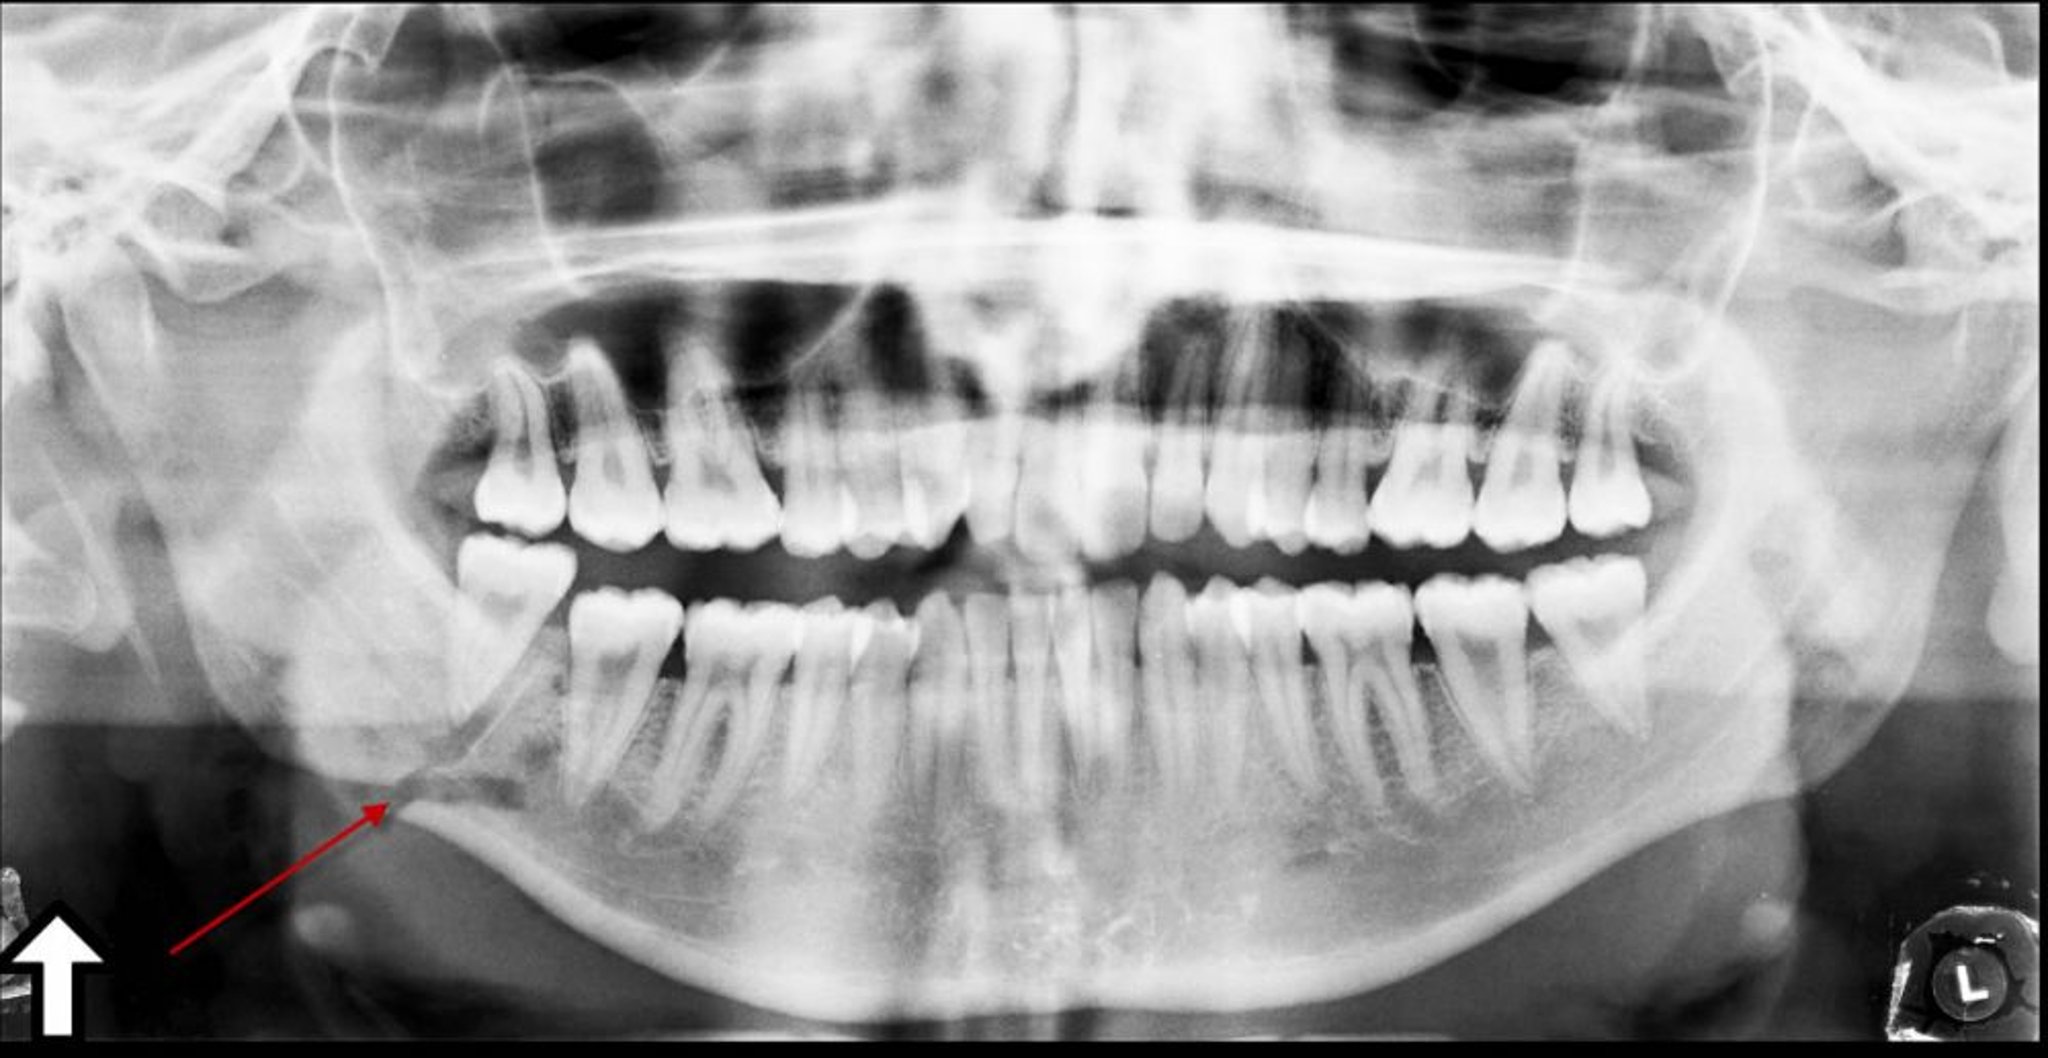

Fractura del ángulo de la mandíbula

Esta radiografía panorámica muestra una zona radiolúcida (flecha) en el ángulo de la mandíbula, que representa una fractura.